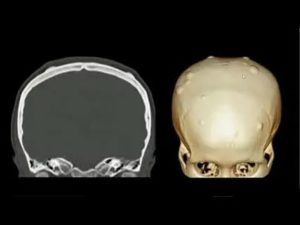

- КТ-томография;

Информативным и предпочтительным методом исследования, помимо рентгена, является компьютерная томография.

На КТ опухоль выявляется в виде однородной, нечетко разграниченной плотной массы. Томография позволяет исключить болезнь Гарднера (множественные остеомы) и точно определить локализацию остеомы.

Если остеома очень маленькая, рентген-диагностика может оказаться недостаточно информативной. Тогда дополнительно проводится компьютерная томография. 3D-реконструкция дает возможность выявить даже крошечные детали структуры остеомы, измерить размеры повреждений.